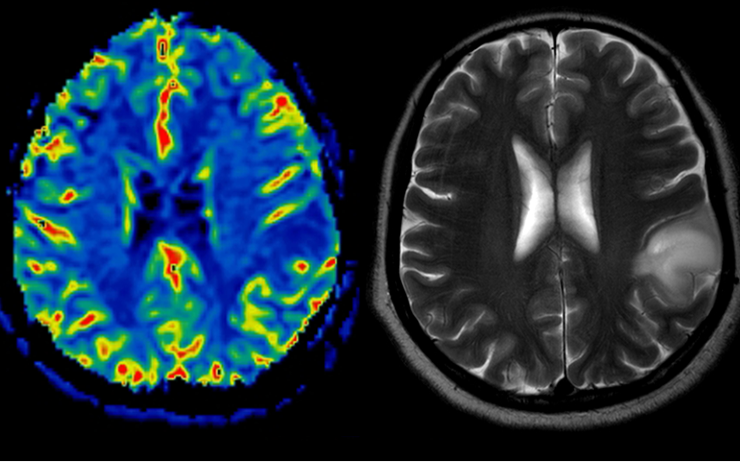

• Neurosciences

• Imagerie médicale